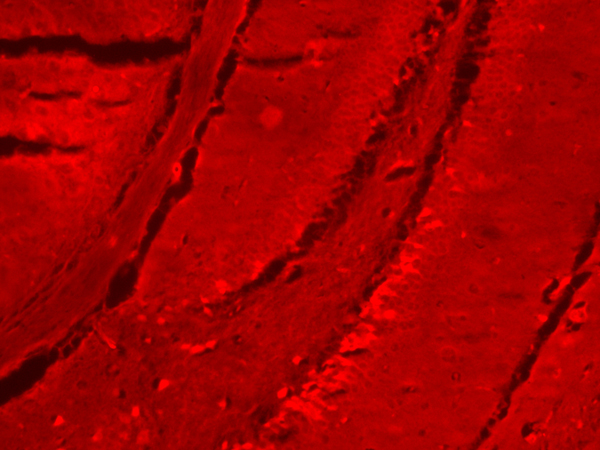

Propidum Iodide Staining of Hippocampus